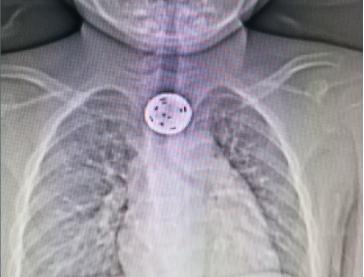

9月20日,一位父亲带着其5岁的娃来到了中山一院惠亚医院耳鼻咽喉科门诊就诊。家长向医生描述说,小孩一直按着喉咙说有点痛,但是具体哪里不舒服又说不出来,已经去了多家医院及诊所,都找不出原因,不知道是不是卡鱼刺了。经我院医生查体,未发现咽部有异物,联想到此前曾接诊过的类似病例,经患儿家属同意后行食管CT检查进一步明确病因。CT结果提示,在食管胸段约胸1、2椎体水平竟然发现了盘状异物残留。

万幸的是,该异物呈纵向位,没有将喉部入口堵死,小孩的呼吸及吞咽并未完全受阻。

我院五官科凌威副主任带领耳鼻咽喉科医生团队为患儿紧急行食道镜下食道异物取出术,仅用时10分钟就将游戏币取出。孩子家长终于松了一口气,并对我院耳鼻咽喉科的诊疗水平表示认可和对医务人员表示由衷的感谢。